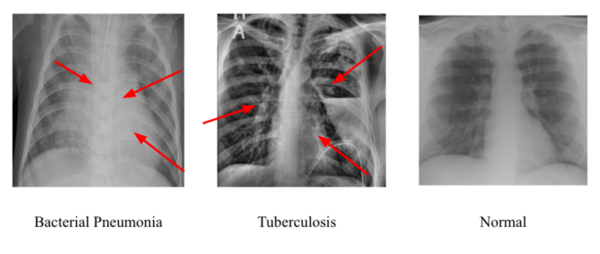

Read More...Determining the best convolutional neural network for identifying tuberculosis and pneumonia in chest x-rays

To best identify tuberculosis and pneumonia diagnoses in chest x-rays, the authors compare different deep learning convolution neural networks.